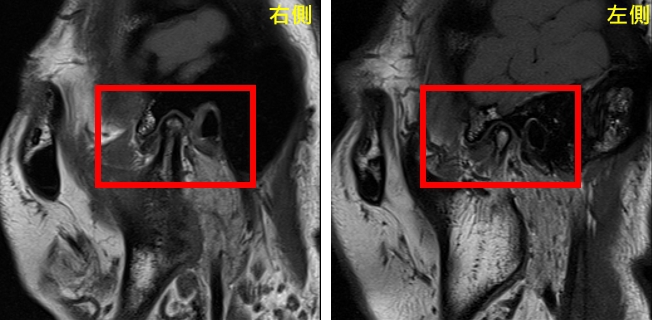

經評估後,由口腔顎面外科呂明怡主治醫師施行關節腔玻尿酸注射,並搭配智慧賦能中心林志峰主任進行震波治療,透過跨專業協作,針對病因進行整體性治療,短短一個月內,曾小姐的顳顎關節疼痛、臉頰緊繃、喉嚨異物感及肩頸痠痛等症狀大幅減輕,隨著持續治療,生活品質顯著提升,也逐漸找回自信與笑容。